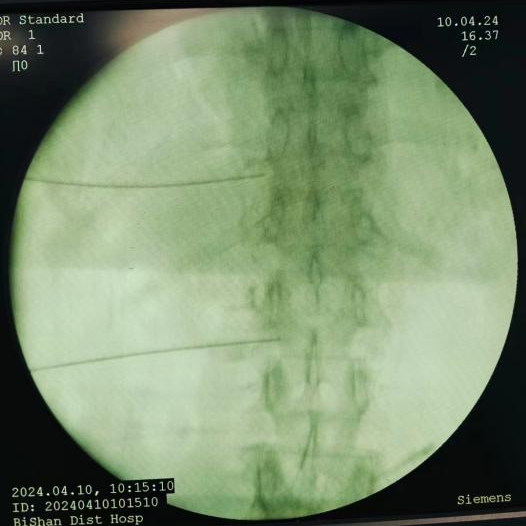

脊髓電刺激植入術(shù):將電極植入脊柱附近硬膜外腔,通過電流刺激脊髓,阻斷疼痛信號傳至大腦,有效治療慢性頑固性神經(jīng)痛。

脊髓電刺激植入術(shù)